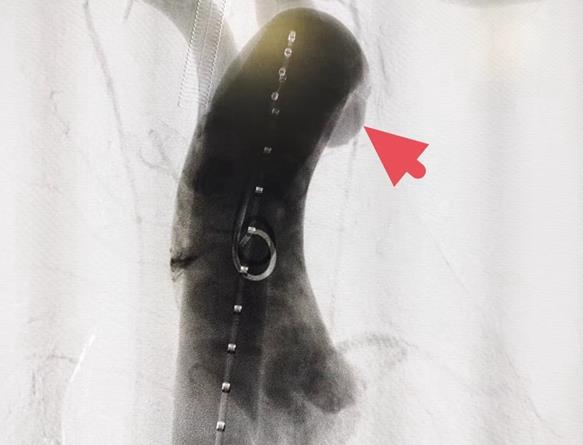

術(shù)中造影

術(shù)后造影

普通外科一病區(qū)·血管外科的醫(yī)生們接到會診通知后,第一時(shí)間參與救治,在科主任徐斌的組織下,就主動脈夾層的診治開展手術(shù)方案討論。隨后在麻醉科主任張志明默契配合下,科室副主任沈濤及魏國醫(yī)師為患者實(shí)施“降主動脈夾層腔內(nèi)隔絕術(shù)”,手術(shù)順利,術(shù)后由ICU醫(yī)生為患者實(shí)施進(jìn)一步治療,以保證后續(xù)骨折手術(shù)順利開展。